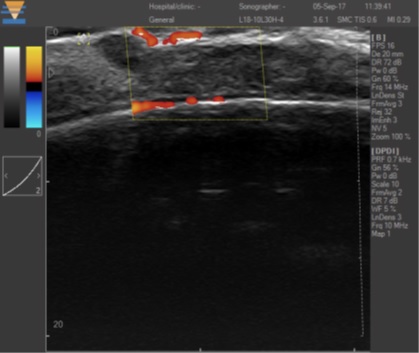

TPM 22兆赫茲超聲,掃描深度達40毫米,分辨率72微米以下,覆蓋HFU和GUS或稱爲合二爲一,同時(shí)具有彩色多普勒功能(néng),必將(jiāng)成(chéng)爲皮膚科和醫學(xué)美容醫生迫切需要的超聲影像可視化、量化手段。